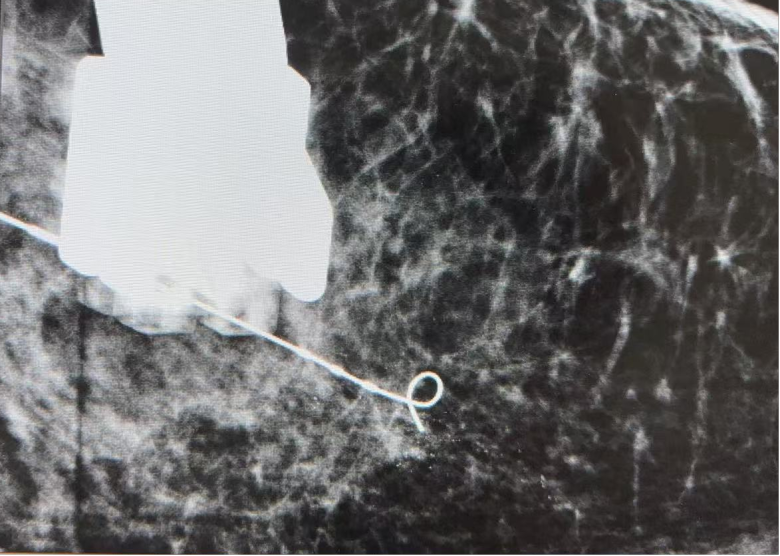

精准定位:通过钼靶引导,在钙化灶中心放置定位针,解决了钙化灶“摸不到”的难题。

▲钼靶精准定位钙化灶并放置定位导丝